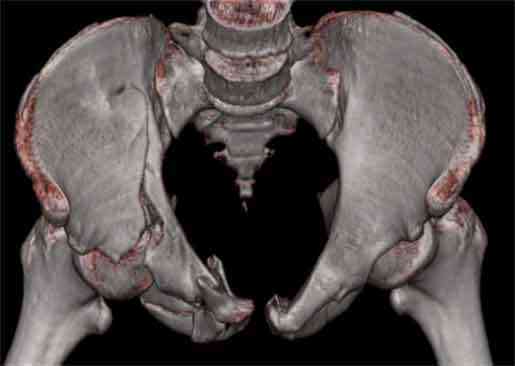

Не смог разглядеть на представленных картинках частичное повреждение левого КП, повреждение Денис1-2 справа? 3Д реконструкции в инлет и боковой проекциях убедительно не демонстрируют типа повреждения задних отделов тазового кольца(справа боковая масса скомпремирована), Наверное, у тебя есть возможность оценить тип перелома крестца по прямой проекции 3Д.

Думаю, что КТ заднего отдела показала бы ясно тип повреждения .

По вертлуге- смог разглядеть только изолированный перелом передней колонны.

Насколько я понял из твоего письма, обращенного к анонимному vit, ты не видишь показаний к реконструкции перелома. Я бы взялся за реконструкцию(илео-ингвинальный доступ), хоть прошел и месяц после травмы: боковая 3Д показывает смещение нагрузочной зоны впадины, что однозначно будет способствовать разрушению хряща головки и впадины( особенно у 16 летнего пациента с ожидаемым высоким уровнем активности) + изменение геометрии впадины за счет неустраненного смещения фрагментов колонны (КТ, 3Д данные).

Сравнивая боковые проекции 3Д реконструкций, разница переломов очевидна: в предыдущем случае на боковой проекции не видно было ступени нагрузочной зоны суставной поверхности - это и объясняет приличную функцию сустава.

В данном случае 3D и корональные срезы КТ менее информативны, чем поперечные. Согласен с левосторенним минимальным повреждением КПС, но не смог уловить перелом крестца.

На 3D по линии перелома ацетабулум возможно сверху в подздошной кости уже есть сращение? или состояние перелома у молодых, после неполного (при пластической деформации) перелома.